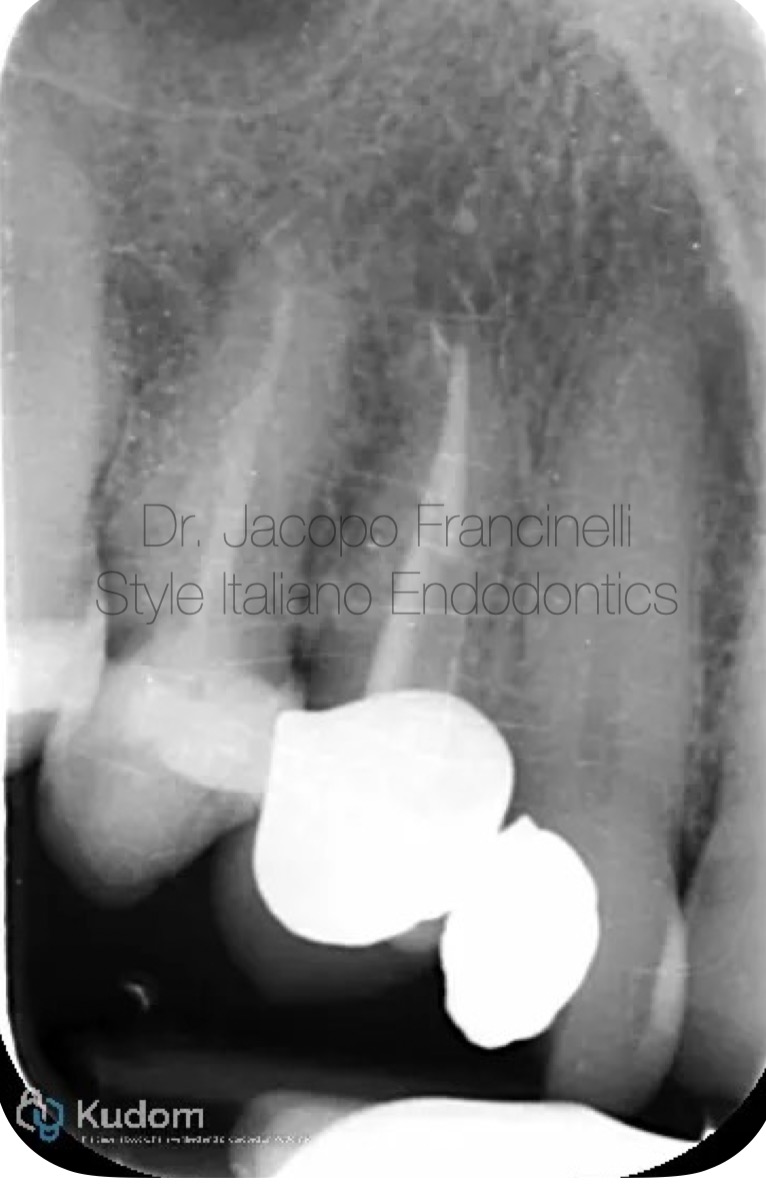

Fig. 1

Pre-operative X-ray:

The initial radiograph shows a maxillary canine with a single, clearly defined canal. The periapical region appears without significant radiolucency, though clinical symptoms indicated pulpal involvement. The canal anatomy appears straight and accessible, making it suitable for efficient mechanical preparation.